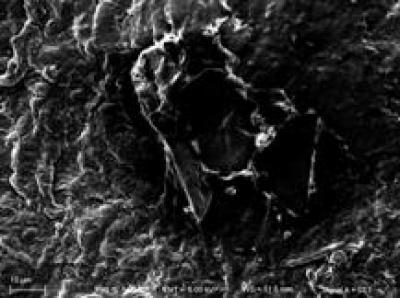

Under scanning electron microscope, this shows a few mildly swollen myelinated nerve fibers obstructed the basilar membrane vessels after poly(lactic-co-glycolic acid) conduit transplantation.

(Photo Credit: Neural Regeneration Research)